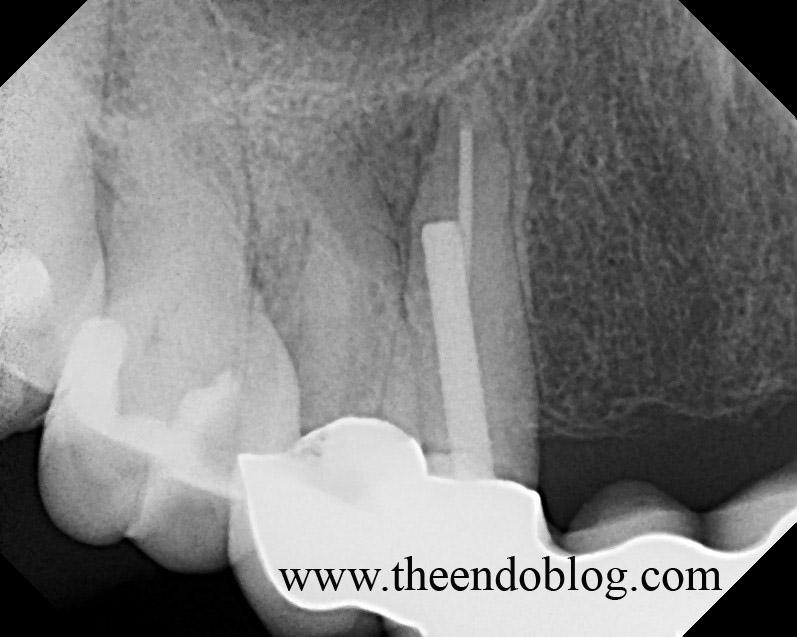

From www.theendoblog.com

The Endo Blog Root Canal Treatment Saves a Perforated Tooth How To Treat Perforation In Rct Root perforation is an artificial communication between the root canal. When you see a root perforation, you may not even be thinking about how to treat that perforated root canal. Regardless of etiology, a perforation should be repaired as soon as possible to discourage further loss of attachment and prevent sulcular. Sonia chopra on december 17, 2023. Reviews factors associated. How To Treat Perforation In Rct.